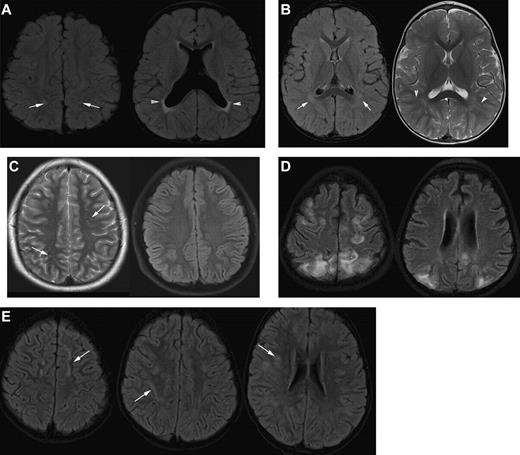

Differential diagnosis of silent infarction (images from patients without SCA). (A) Mimics of SCI: periventricular leukomalacia (PVL). A 20-month-old boy with cerebral palsy characterized by spastic diplegia. Axial FLAIR MR images illustrate classic findings of PVL. The image on the left is at the level of the centrum semiovale and demonstrates bilateral hyperintensities in the parietal lobe white matter. This appearance of the white matter overlaps with the presentation of SCI. The image on the right at the level of the basal ganglia illustrates dysmorphic lateral ventricles, thinning of the periventricular white matter and periventricular signal hyperintensity in a predominantly posterior distribution. Taken together, the images are consistent with the diagnosis of PVL in the setting of prematurity and cerebral palsy rather than SCI. (B) Terminal zones of myelination. A 2-year-old boy with a normal MRI of the brain. The Axial FLAIR MR image (left) shows ill-defined hyperintensity bilaterally in the deep white matter adjacent to the atria of the lateral ventricles (arrows). The T2-weighted image on the right illustrates that there are well-defined linear perivascular spaces (arrowheads) traversing the area of vague hyperintensity. This combination of findings is classic for the terminal zones of myelination, the last areas of the deep white matter to myelinate and displace free water. The terminal zones of myelination remain prominent through the second year of life and become progressively less conspicuous over time. They may be visible into the middle of the first decade of life. (C) Virchow-Robin spaces. A 12-year-old boy withT2-weighted (left) and Axial FLAIR (right) MR images with a normal MRI. The T2-weighted images reveal multiple punctuate white matter hyperintensities that suppresses on FLAIR indicating that the hyperintensities are indistinguishable from cerebrospinal fluid. The fluid attenuation feature of the FLAIR image helps to differentiate perivascular (Virchow-Robin) spaces from SCI. The arrows illustrate another feature of perivascular spaces which is that they appear linear when running within the slice. (D) Posterior reversible encephalopathy syndrome (PRES). A 14-year-old girl with altered mental status and seizures. Axial FLAIR MR images demonstrate hyperintensities bilaterally in the subcortical white matter and overlying cortex with predominant subcortical involvement. The distribution of the signal abnormalities is predominantly posterior and peripheral, a typical distribution for PRES. In contradistinction, SCIs favor the deep white matter of the frontal lobes. Nevertheless, clinical context is the key to differentiating PRES from SCIs. This is especially challenging in patients with SCD because they are prone to development of PRES and SCI. (E) Acute disseminated encephalomyelitis (ADEM). A 5-year-old boy with fever and headache. Axial FLAIR MR images demonstrate patchy, bilateral hyperintensities in the white matter of the centrum semiovale and corona radiata (arrows). Although the image on the left could be confused for SCI in the frontal border zone distribution, the middle and right image show subcortical and patchy hyperintensities that would be atypical in location, size, and lesion definition for SCI. The clinical information is the key to distinguishing lesions of ADEM from SCI.